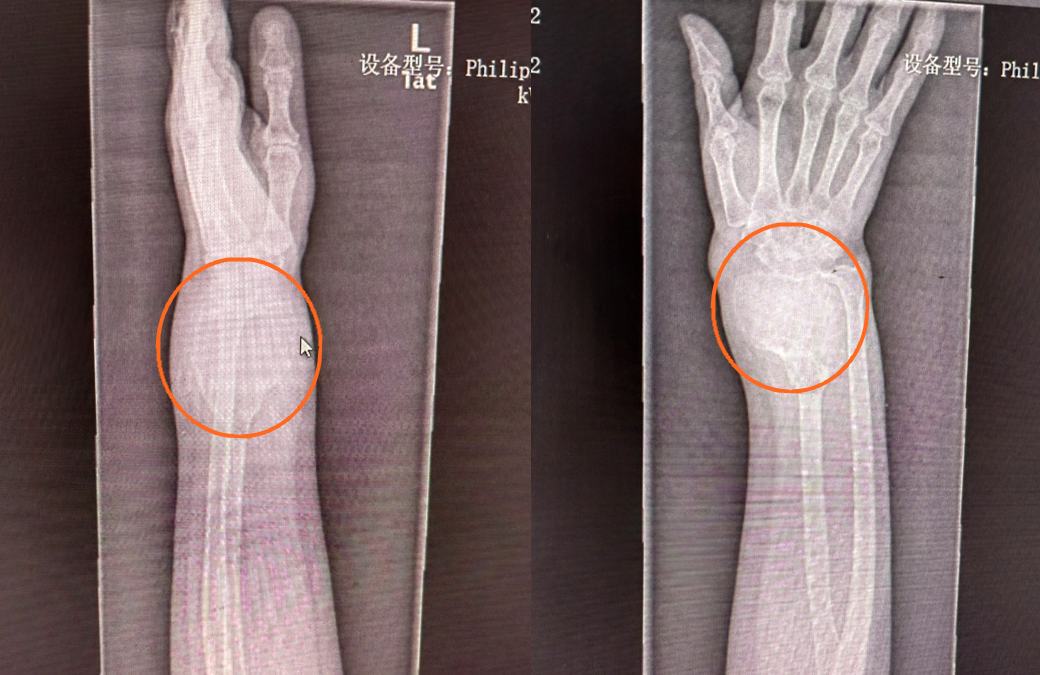

“前兩天,患者來院進(jìn)行手術(shù)后的最后一次復(fù)查,前臂移植骨已經(jīng)愈合,腕部的穩(wěn)定性良好,能夠進(jìn)行一般的日?;顒?。右腿取小腿骨頭的地方也沒有任何不適,膝關(guān)節(jié)屈伸活動穩(wěn)定,行走活動正常?!笔中g(shù)的主刀醫(yī)生官常和提及這例橈骨下端骨巨細(xì)胞瘤切除手術(shù)+腓骨移植重建腕關(guān)節(jié)術(shù)的成功,略帶些興奮。

51歲的患者稅女士,一年前左前臂遠(yuǎn)端不明原因的出現(xiàn)一個包塊,她以為就是個軟組織包塊,沒太當(dāng)回事,包塊越來越大,到醫(yī)院拍片子一看,整個橈骨下段長達(dá)十多公分的骨頭上長的包塊已經(jīng)像個氣球一樣?!斑@個包塊是骨巨細(xì)胞瘤,是原發(fā)性骨腫瘤,長這么大,還是比較少見的,雖然是骨的良性病變,具有較強(qiáng)的侵襲性和轉(zhuǎn)移能力,會對骨質(zhì)有明顯的破壞性,需要進(jìn)行手術(shù)治療?!惫俪:歪t(yī)生看了片子跟患者交流。